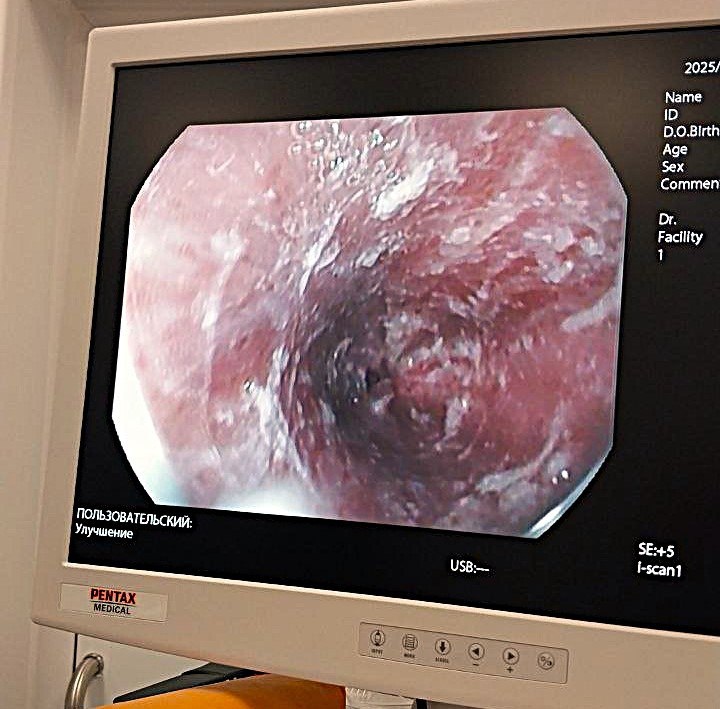

Оренбургские врачи спасли двухлетнего ребёнка после химического ожога

Врачи областной детской клинической больницы спасли 2-летнего оренбуржца, который выпил «Азелит Ультраконцентрат» и получил сильный ожог слизистой. Ему предстоит длительное восстановление.

-Химические ожоги пищевода и желудка — проблема очень серьёзная. С приходом тепла начался сезон генеральных уборок, и родители детей активно используют чистящие средства. Но порой забывают о правилах безопасности, считает заведующий эндоскопическим отделением ОДКБ Андрей Бобров.

По его словам, самые распространённые причины ожогов – выпитая детьми бытовая химия, которая содержит щёлочь. Такие растворы, если их принять внутрь, вызывают появление рубца в месте заживления пищевода. Это приводит к нарушению глотания и требует сложных операций. Врач рекомендует срочно вызывать скорую помощь, если ребёнок отравился подобным средством.